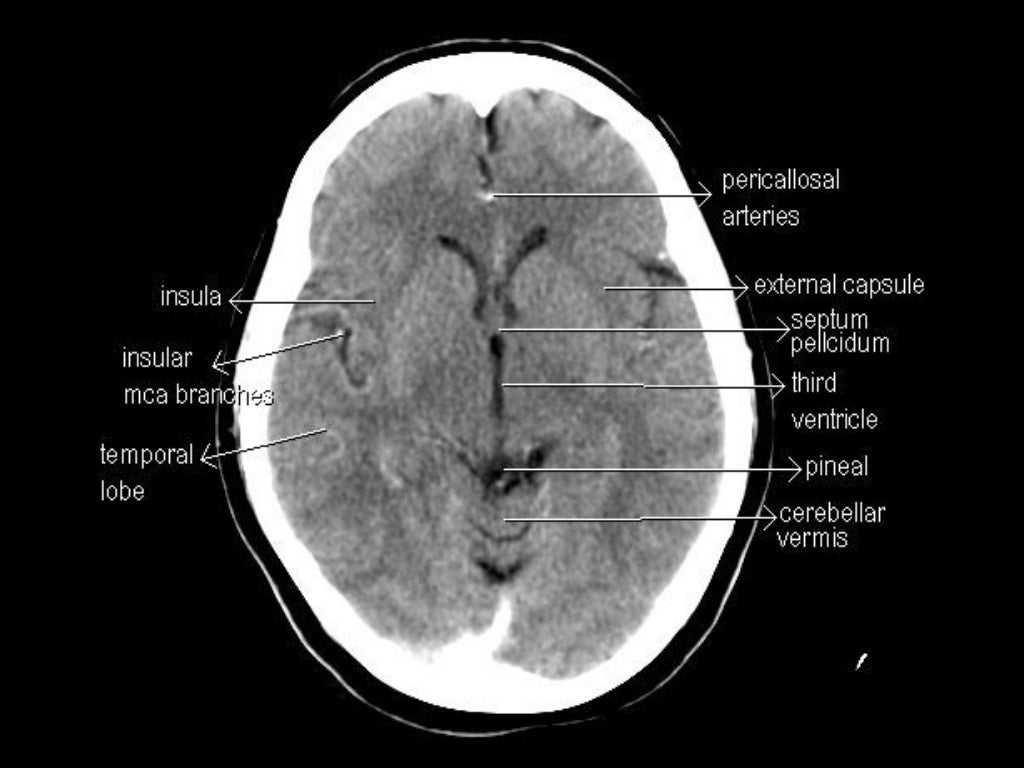

CT Anatomy

Normal CT BRAIN Ct Anatomy Of Brain Slideshare The document discusses the radiological anatomy of a normal ct brain scan. It begins by describing the lobes of the brain and surfaces visible on ct. Identify the ct anatomy of the brain 3. This document provides information about brain anatomy, including the embryology and major. Ct scans are useful for. Published by angelina annabella andrews modified over 6 years. Ct Anatomy Of Brain Slideshare.

CT Scan Tips & Protocols CT BRAIN ANATOMY Ct Anatomy Of Brain Slideshare Anatomy of normal ct brain. Identify the ct anatomy of the brain 3. Review the basics of ct imaging 2. It describes the skull bones and sutures that. Ct scans are useful for. The document discusses the radiological anatomy of a normal ct brain scan. This document provides information about brain anatomy, including the embryology and major. Published by angelina. Ct Anatomy Of Brain Slideshare.

CT Anatomy Ct Anatomy Of Brain Slideshare It begins by describing the lobes of the brain and surfaces visible on ct. Anatomy of normal ct brain. This document provides an overview of the radiological anatomy of the brain through computed tomography (ct) imaging. Hounsfield units and densities of brain tissues on ct are defined. The document discusses the radiological anatomy of a normal ct brain scan. Ct. Ct Anatomy Of Brain Slideshare.